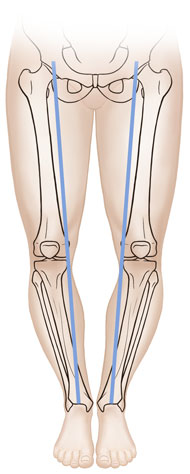

If your child’s legs curve outward, they have bowlegs. If your child’s knees come together and the lower legs point outward, they have knock knees. Often, a child will start out with bowlegs, the legs may straighten, then the child may become knock-kneed. Your healthcare provider will examine your child’s legs and may X-ray them to make sure there isn’t a structural problem.

| Bowlegs. |